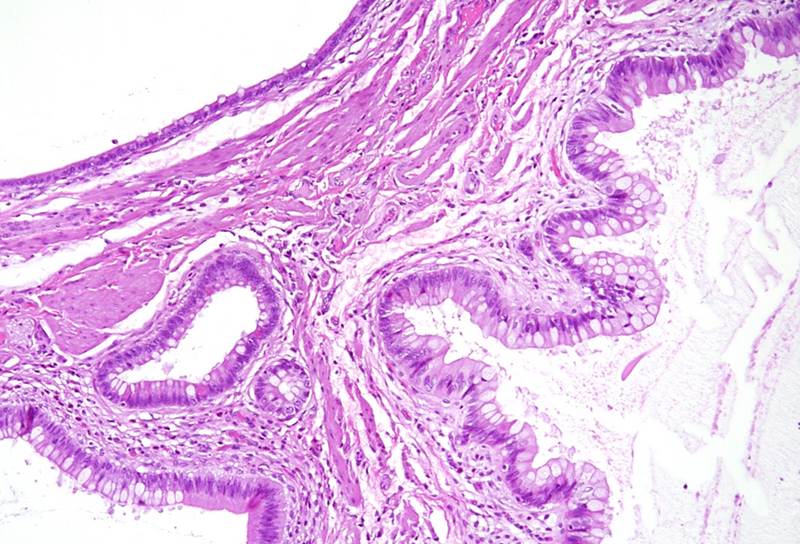

Polypoid lesion at the anorectal junction in a 47 year-old male.

Proctitis cystica profunda.

Microscopically, one specimen disclosed cystically dilated structures of variable size underneath regular colonic  / anal mucosa (Panels A-B). The cysts are filled with mucin, and the epithelial lining is of intestinal type, showing reactive changes, yet no dysplasia in the presence of mixed unspecific inflammation (Panels C-D).

Histologically, it is characterized by the presence of either localised, segmental, or diffuse mucus-filled cysts of the deep submucosa and even muscularis propria. Size of the cysts may differ, depending on localisation and diffuse morphology, lesions can measure up to even 2 cm. The lining epithelium lacks atypia, with only minor nuclear irregularities in case of secondary inflammatory changes. The overlying mucosa is intact. Surrounding areas may contain fibrosis and hemosiderin laden macrophages. The cysts may rupture causing mucin dissemination into the surrounding tissue, potentially followed by degenerative calcification. Differential diagnosis mainly includes mucinous adenocarcinoma, which may be identified by nuclear dysplasia and/or desmoplastic response.